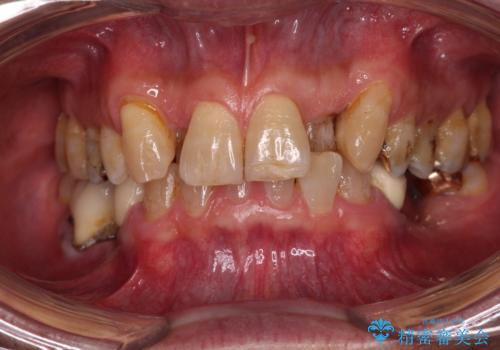

- 他院で矯正治療を行った後、保険診療で装着した前歯のクラウンの変色を気にして来院された患者様です。

保険診療では樹脂を用いた素材で製作するため、水分が吸収されやすく、一緒に色素が取り込まれるために変色をしてしまいます。

また、裏打ちに主に銀を用いた金属材料を使用するため、金属自体が黒くなったり、イオンとなり溶け出したりして、歯肉ラインが黒くなってしまうことがあります。

矯正治療を始める前から、前歯の変色が気になっていたようですが、矯正治療が終わるまで待つようにと言われたとのことでした。